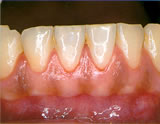

- 歯肉炎

歯茎が腫れ、所々に赤黒い部分が

できています。